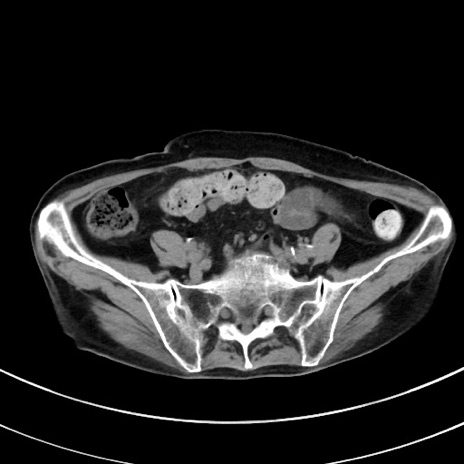

症例33(横断像)

【症例】70歳代 女性

【主訴】心窩部痛

【現病歴】延髄病変の精査・加療にて神経内科入院中。本日より心窩部痛あり。

【身体所見】右下腹部を中心に圧痛と反跳痛あり。

【データ】WBC 10900、CRP 0.02